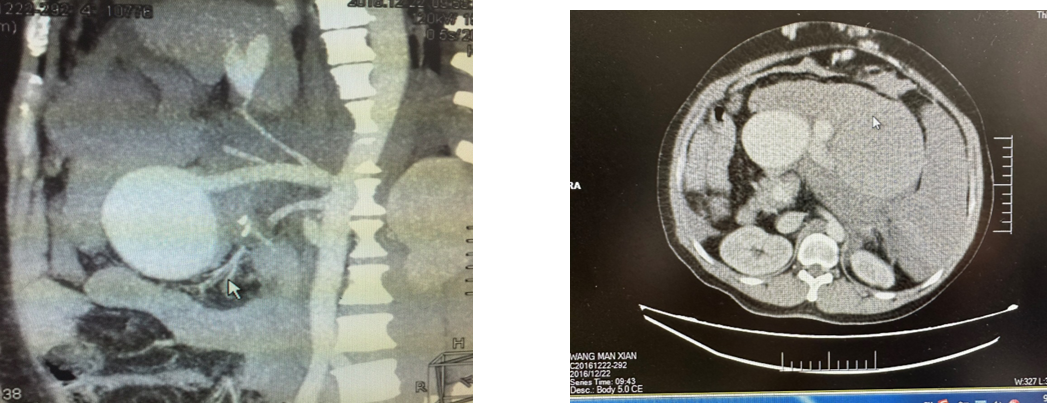

病例6 脾动脉瘤Viabahn支架隔绝

图为:术后复查

病例7 脾动脉瘤戴膜支架隔绝